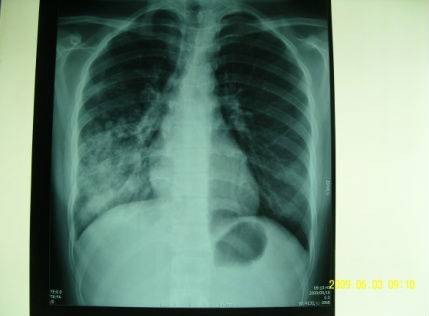

提问:高烧不退伴咳嗽10余天。病情描述(主要症状、发病时间):高烧39度伴咳嗽,无痰,57日,突然高热,无其他阵发性咳嗽,咳嗽时腰痛厉害。阿莫仙、阿奇,现用美平静滴,体温不降。中药吃了2付。血沉110 CRP112,其他均在正常之内,CT:右下肺炎症。

2009-05-26我女儿的病现在基本好了,我给他拍了胸片,有点支气管炎,原先的阴影基本消失,孩子已上学,十万分的感谢陶教授的救命之恩!

治疗前

治疗后

按:急性重症肺炎中期、极期的肺部影像学特点绝大部分患者出现弥漫性肺部炎症异常表现。病变形态分为斑片状影,大片状影,斑片融合影像。病变密度为肺实变密度及磨玻璃密度影,肺纹理增粗模糊,肺实变的影像和临床表现相关联,持续高热时,肺部影像最为严重和广泛。此时西医治疗要点:要及时适量、足量使用糖皮质激素。中医辨证:疫毒犯肺,邪在气分。治则:清瘟泻热解毒,宣肺平喘。中西医结合治疗,短期内炎症吸收迅速,病情好转,没有遗留,邪去正安。